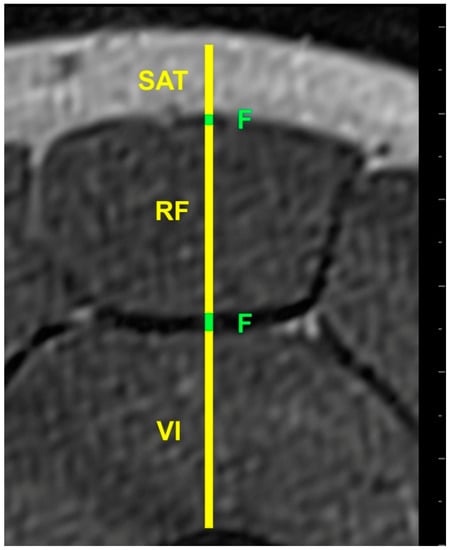

2.4. MRI Acquisition

2.5. Image Processing

- Worsley, P.R.; Kitsell, F.; Samuel, D.; Stokes, M. Validity of measuring distal vastus medialis muscle using rehabilitative ultrasound imaging versus magnetic resonance imaging. Man. Ther. 2014, 19, 259–263. [Google Scholar] [CrossRef] [PubMed]

- Walton, J.M.; Roberts, N.; Whitehouse, G.H. Measurement of the quadriceps femoris muscle using magnetic resonance and ultrasound imaging. Br. J. Sports Med. 1997, 31, 59–64. [Google Scholar] [CrossRef] [PubMed]